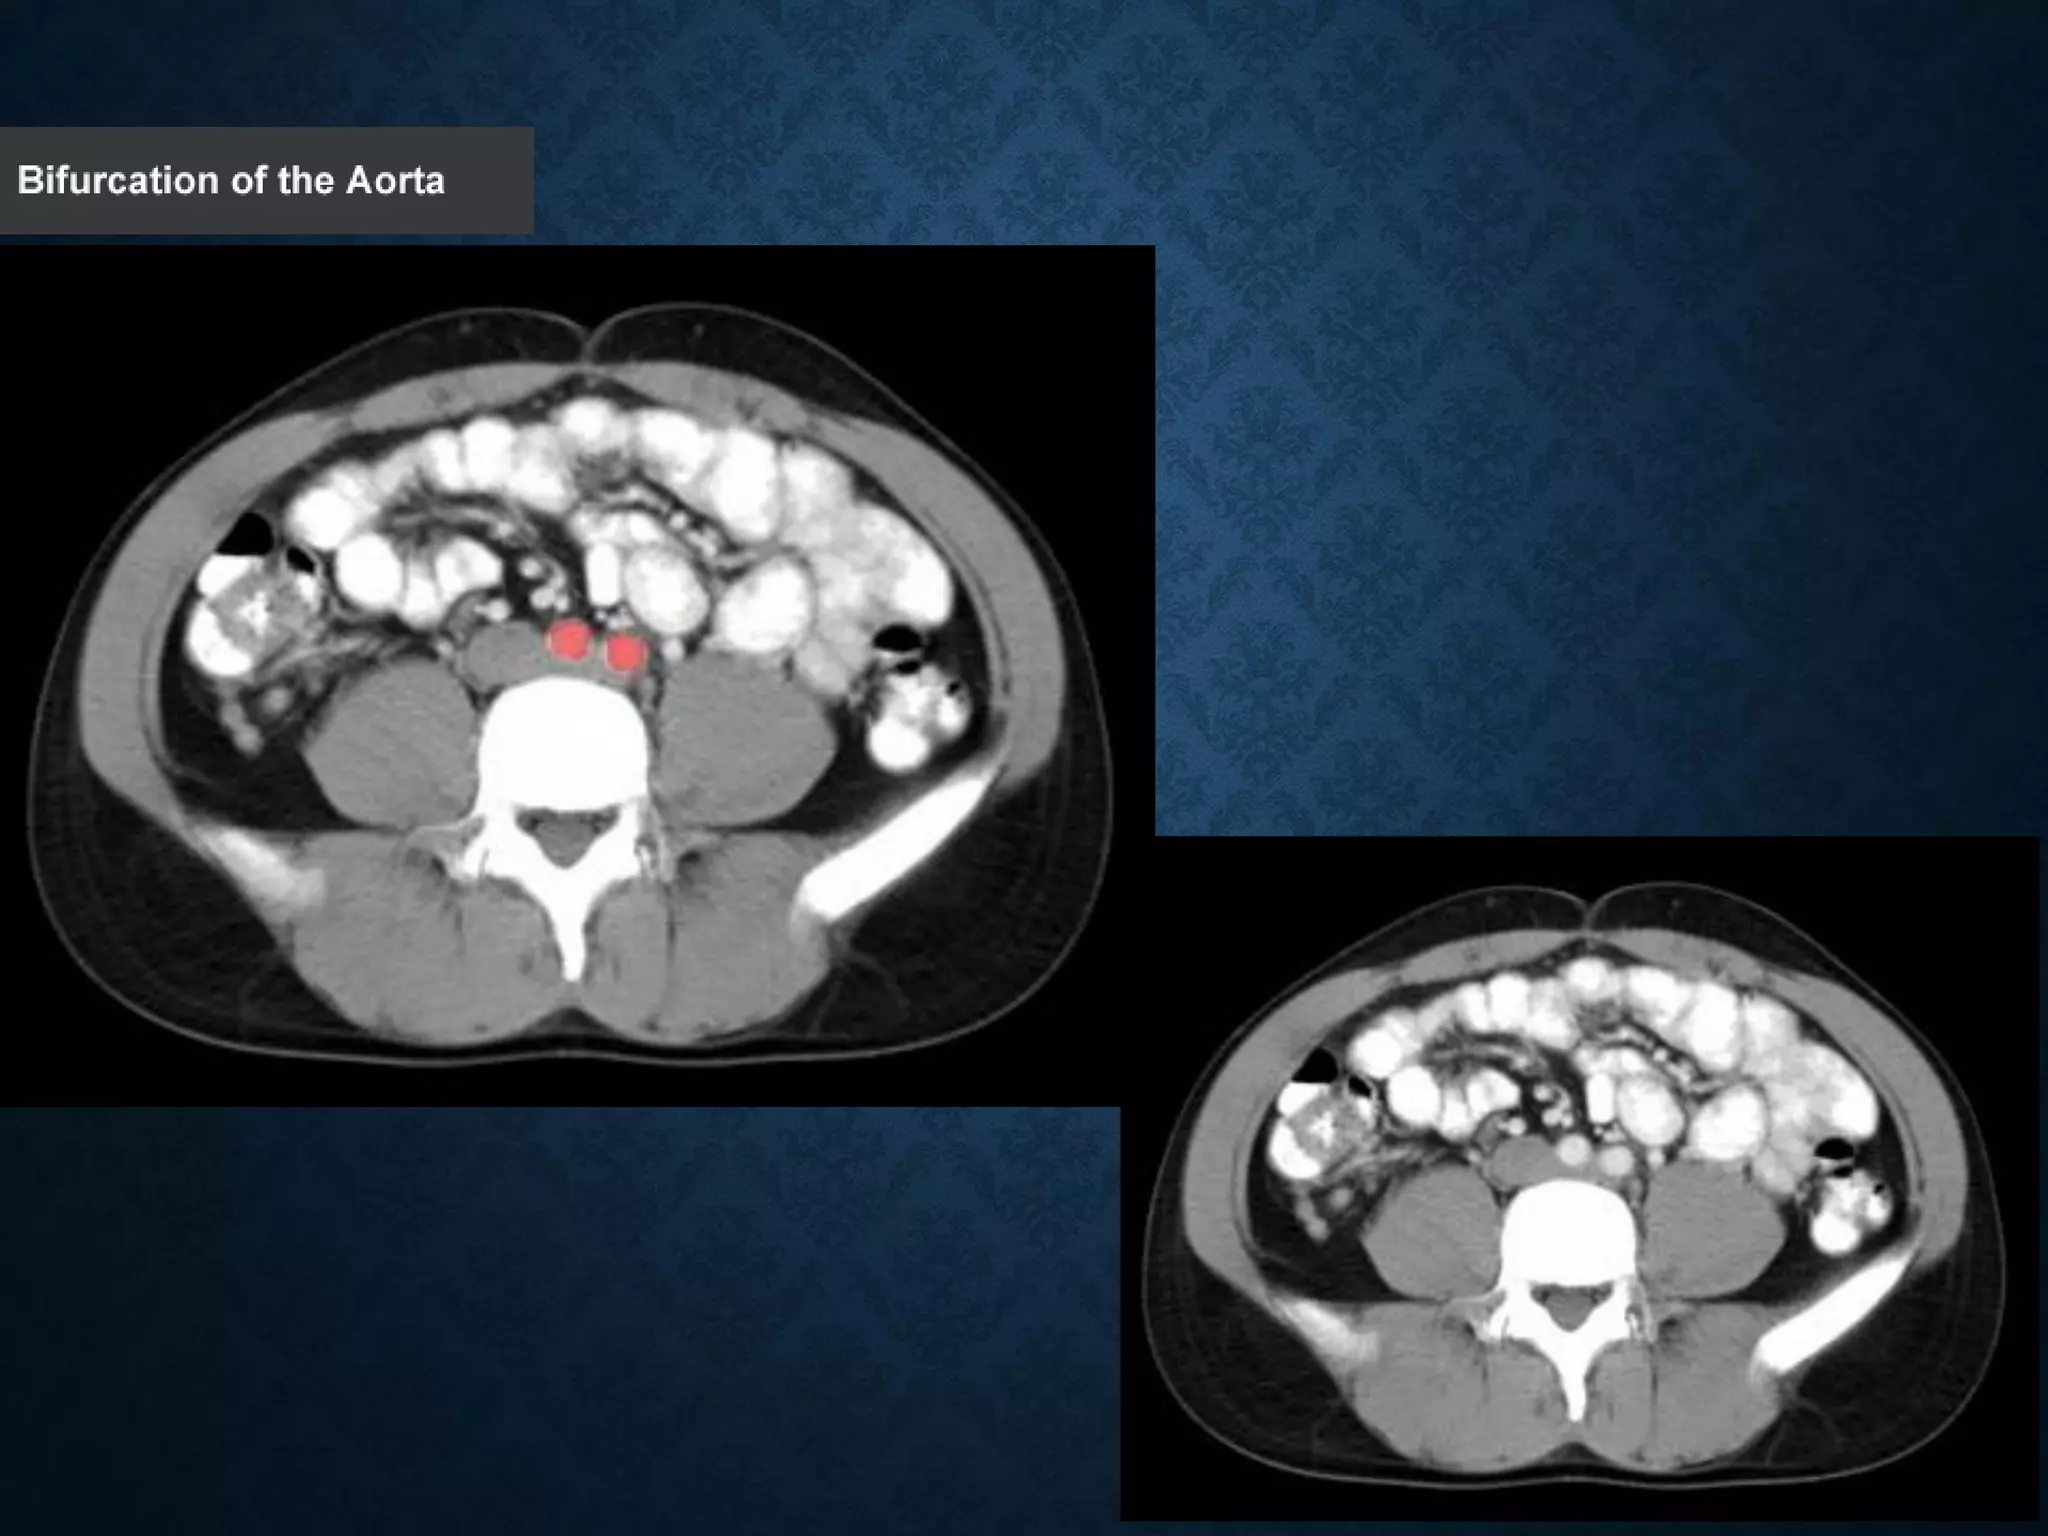

ABDOMINAL AORTA

•Bifurcation of aorta:L4

• Note that the bifurcation (union) of the inferior vena cava is at L5and

therefore below that of the bifurcation of the aorta)

ABDOMINAL AORTA origin: Continuationof descending thoracic aorta at T12 • course: descends anterior and slightly to the left of the lumbar vertebral bodies. •Bifurcation of aorta:L4 • Note that the bifurcation (union) of the inferior vena cava is at L5and therefore below that of the bifurcation of the aorta)